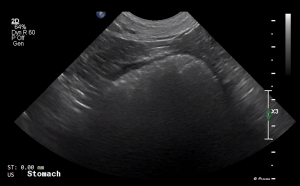

SIMON Ultrasound Database

This ultrasound database is a free resource for students and doctors!

Our collection includes videos of dogs, cats, horses, cows, humans, and many other species!